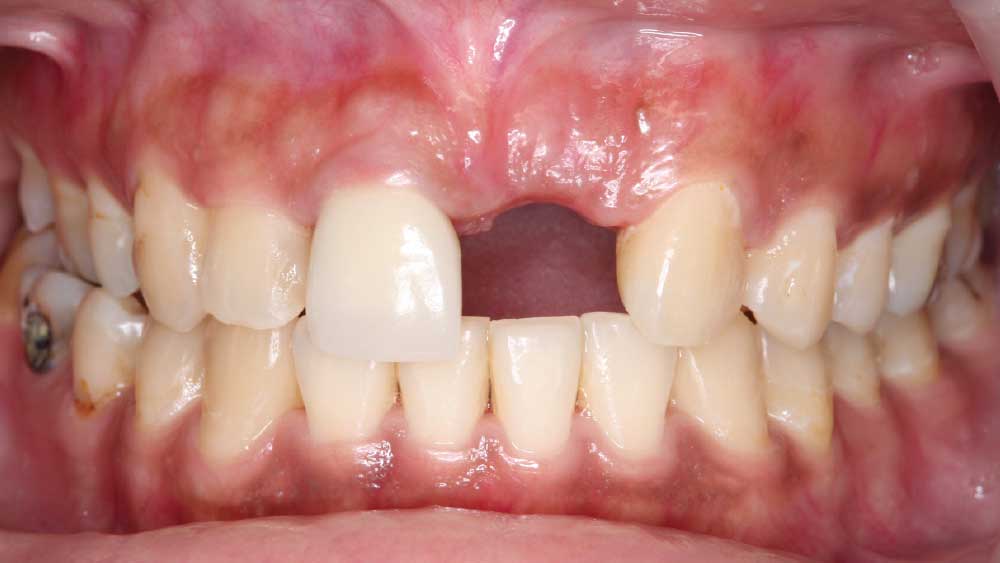

For the first time in many years, Maria is all smiles. It is a dramatic difference from where she was just four months ago. When she arrived in my office, she was so self-conscious I could barely get her to open her mouth. Simple daily tasks like talking and eating had become problematic due to a fractured tooth that was barely attached by an endodontic post. It was so mobile that during our initial visit, Maria was afraid it would fall out while she spoke.

BRIDGING THE GAP WITH BRUXZIR® ESTHETIC

After conducting a thorough diagnostic examination, a vertical root fracture was noted, leaving the #9 central incisor malaligned and unstable. Due to the presence of significant vertical bone loss, extensive treatment for guided bone regeneration and a connective tissue graft would have been required prior to implant placement. After the patient was consulted on these factors, she opted against implant treatment. Once we discussed the remaining options, she decided on a bridge from #8–11 and a veneer on #7. Because she was congenitally missing tooth #10, placing a bridge to restore the edentulous area required preparing the adjacent canine and reshaping it to look like the missing lateral. I selected BruxZir® Esthetic Solid Zirconia as the best material to restore her beautiful smile. Not only does BruxZir Esthetic have superior strength compared to similar all-ceramic materials such as IPS e.max®, but it also has a translucent, natural-looking appearance. Sometimes clinicians think it is risky to do an all-ceramic bridge, but with a strong material like BruxZir Esthetic that has an average flexural strength of 870 MPa, doctors can confidently seat an anterior bridge that will produce long-lasting results. BruxZir has become such a popular material for dentists that it has been utilized to successfully fabricate more than 1.2 million bridges.